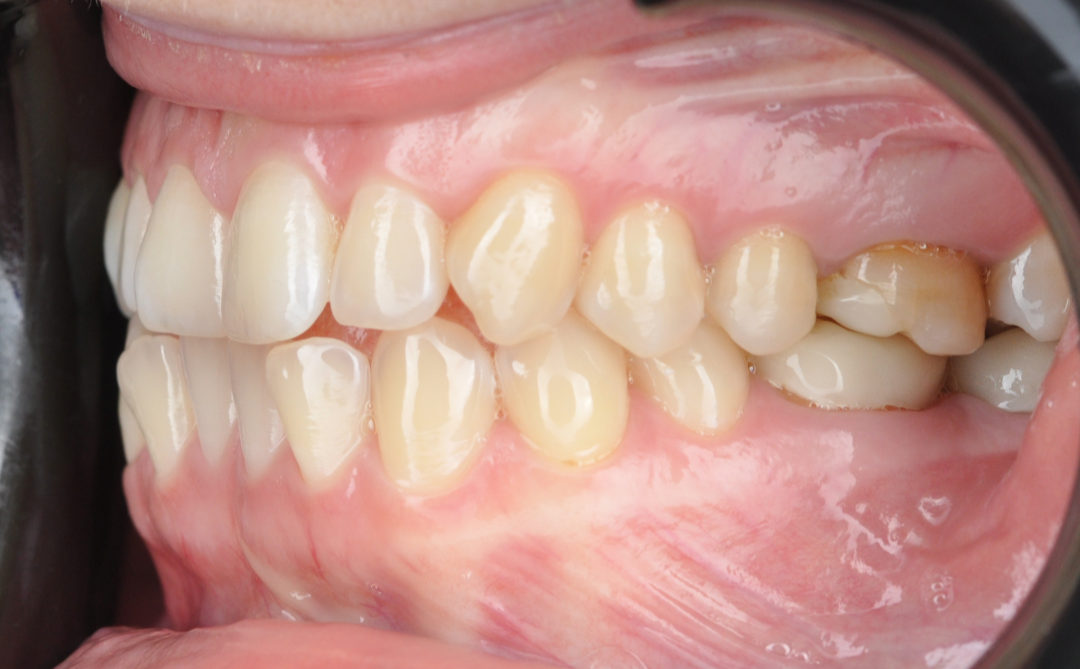

Этап №3

Ортодонтическая коррекция.

Стоматолог-ортодонт зафиксировал комбинированную брекет-систему (сверху керамические, а снизу – металлические брекеты).

Ключевые задачи ортодонта:

- Исправление прямого прикуса (одной из частых причин дисфункции ВНЧС).

- Изменение положения зубов.

- Доведение контактов челюстей до физиологически правильного смыкания.

Эстетика

Исправлен прямой прикус, восстановлена форма резцов, а улыбка стала не только красивой, но и здоровой с точки зрения биомеханики.